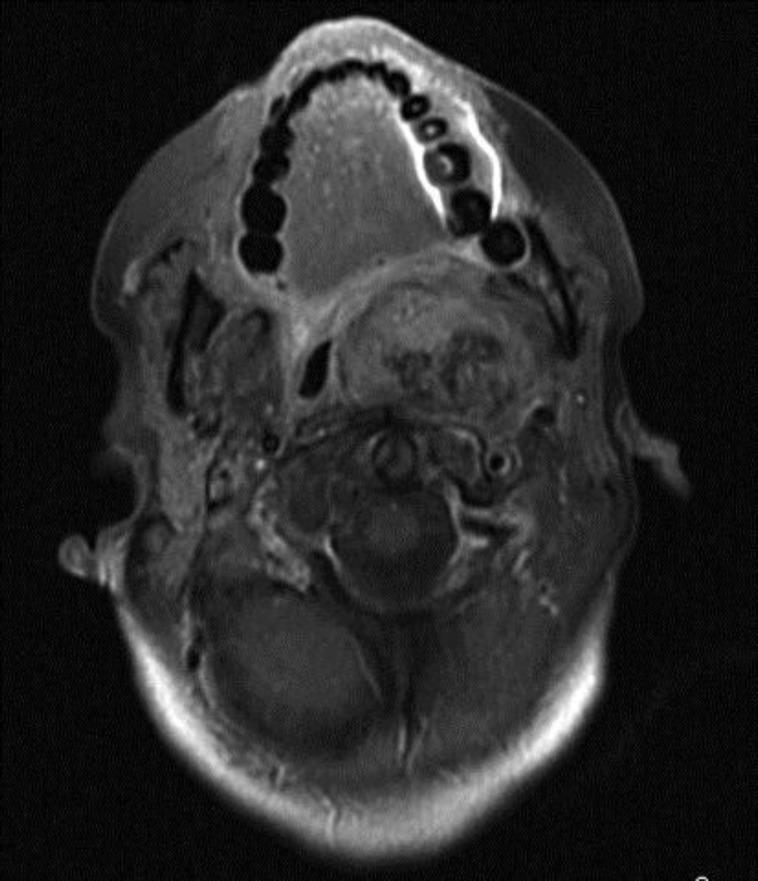

We report on a patient who presented to the Ear, Nose and Throat (ENT) clinic with swelling of the neck, dysphagia, headache, dyspnea and stridor. Imaging studies revealed an expansive heterogeneous process to the left retropharyngeal region. The mass was ovoid in shape, displaying moderate enhancement after intravenous contrast administration. Subsequently, a biopsy revealed the presence of undifferentiated sarcoma. The patient was treated with chemotherapy followed by radiation therapy, but follow-up exams at 6 months posttreatment revealed that while the tumor was stable, it persisted. Consequently, the patient was enrolled in a palliative care and pain control program and is currently being followed.

摘要

我们报告了一名患者,该患者因颈部肿胀、吞咽困难、头痛、呼吸困难和喘鸣而就诊于耳鼻喉科诊所。影像学检查显示左咽后区有一个膨胀性的异质性病变。肿块呈椭圆形,静脉注射造影剂后显示中度强化。随后,活检显示存在未分化肉瘤。该患者接受了化疗,随后进行了放射治疗,但治疗后6个月的随访检查显示,虽然肿瘤稳定,但仍然存在。因此,该患者参加了姑息治疗和疼痛控制项目,目前正在接受随访。